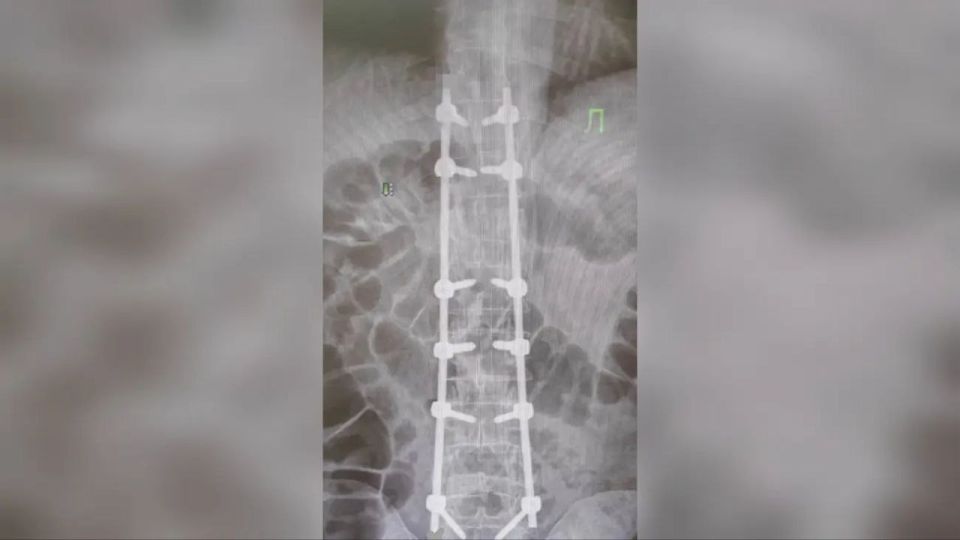

В нейрохирургическом отделении республиканской клинической больницы успешно проведена сложная операция, позволившая вернуть способность к самостоятельному передвижению пациенту с тяжёлой травмой позвоночника.«Мужчина поступил с диагнозом...